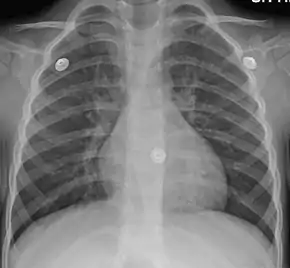

| Figure A shows the location of the lungs and bronchial tubes. Figure B is an enlarged view of a normal bronchial tube. Figure C is an enlarged view of a bronchial tube with bronchitis. | |

In more than 90% of cases, the cause is a viral infection.[1] These viruses may be spread through the air when people cough or by direct contact.[2] Risk factors include exposure to tobacco smoke, dust, and other air pollution.[2] A small number of cases are due to high levels of air pollution or bacteria such as Mycoplasma pneumoniae or Bordetella pertussis.[1][9] Diagnosis is typically based on a person's signs and symptom.[4] The color of the sputum does not indicate if the infection is viral or bacterial.[1] Determining the underlying organism is typically not needed.[1] Other causes of similar symptoms include asthma, pneumonia, bronchiolitis, bronchiectasis, and COPD.[1][7] A chest X-ray may be useful to detect pneumonia.[1]

- A chest X-ray is useful to exclude pneumonia which is more common in those with a fever, fast heart rate, fast respiratory rate, or who are old.[7]